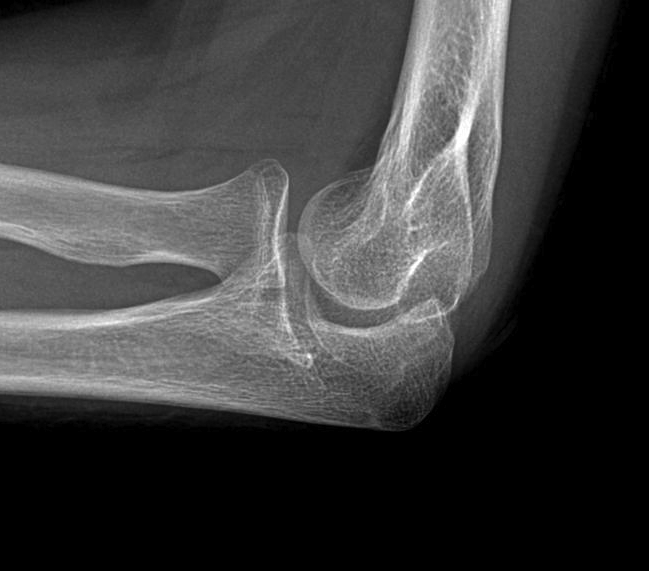

X-ray

Early stage

- preserved radiocapitellar and ulnohumeral joints

- osteophytes of the olecranon and coronoid

Lateral xray demonstrating olecranon and coranoid osteophytes